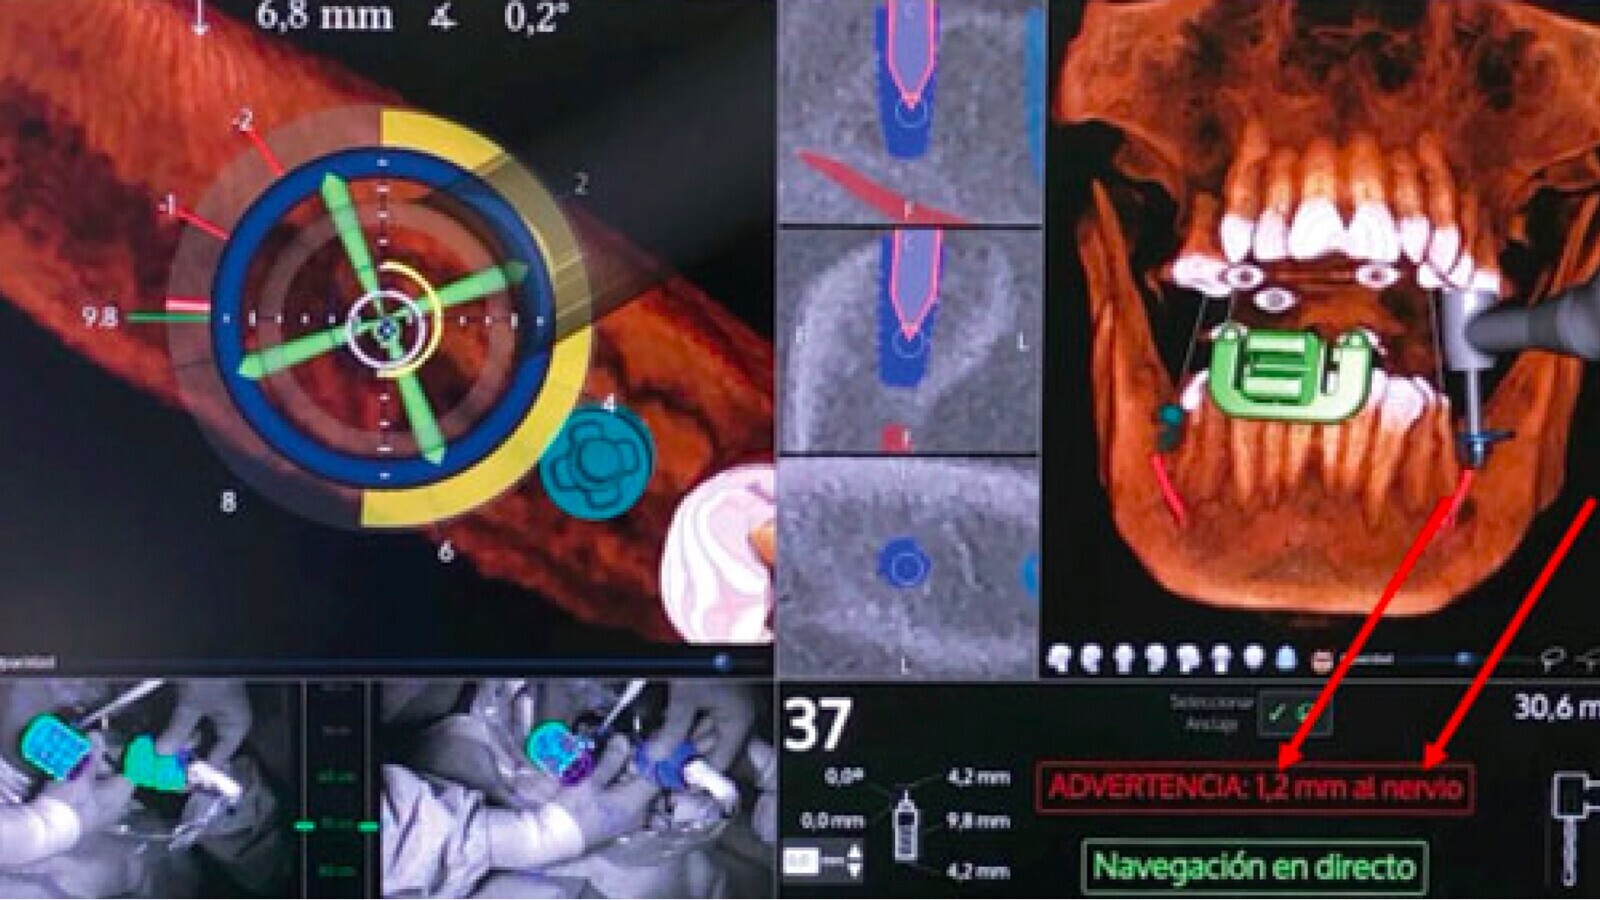

Figura 2. Pantalla de control de una cirugía guiada para implantes.

La cirugía navegada nos proporciona una referencia tridimensional, de manera continua de los instrumentos que estemos empleando y de la anatomía del paciente. El cirujano puede ver exactamente en dónde está la fresa o el implante a medida que se avanza y de esta manera se pueden confirmar el ángulo y profundidad de manera instantánea, algo que mejora la seguridad y reduce enormemente el margen de error.

Figura. 3 Colocación de un implante lateral al nervio dentario (izquierda). Figura 4. Proximidad extrema del implante al nervio dentario (derecha).

• Implantología en casos complejos: cuando tenemos poco volumen de hueso o existen estructuras anatómicas de riesgo, el nervio dentario, o seno maxilar, la navegación en tiempo real evita sorpresas inesperadas.